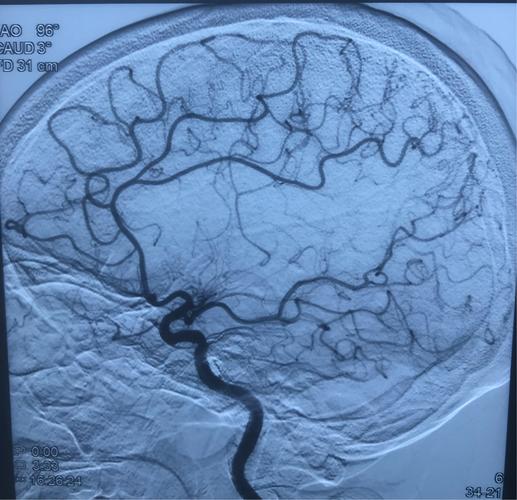

通过血管成像,对动脉瘤的诊断已经很容易明确, 随着手术技术的成熟和手术材料的更迭,手术治疗方案也逐渐向科学化、个体化发展。然而,在很多情况下,aSAH带来的各种并发症可以对患者预后产生决定性的影响。